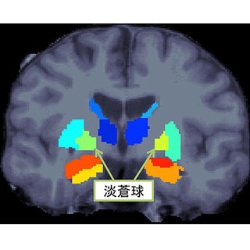

脳の特定部体積に左右差 統合失調症患者、阪大など発見

阪大など、統合失調症患者の脳で左右の体積がアンバランスな部位を発見

大阪大学(阪大)と東京大学(東大)は1月19日、統合失調症では淡蒼球という脳領域の体積に左右差があることを発見したと発表した。 同成果は阪大大学院連合小児発達学研究科の橋本亮太 准教授、東大大学院医学系研究科精神医学分野の岡田直大氏、笠井清登 教授らの ...マイナビニュース ·